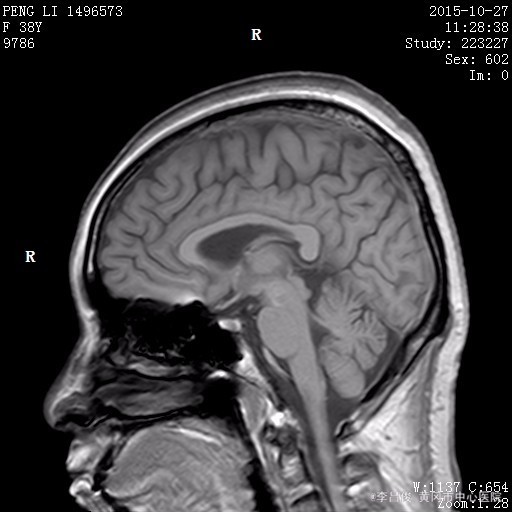

体格检查:BP130/90mmHg、 HR90次/分、 R16次/分, T36.5℃ 神清,精神欠佳,步入病房,查体合作。全身皮肤巩膜无明显黄染,结膜充血,全身多处淤青。颈软,甲状腺未及,双肺呼吸音清,未闻及明显干湿啰音,心律齐,各瓣膜区未闻及明显病理性杂音,腹软,肝脾肋下未及,双下肢不肿。 专科情况:神清,双侧瞳孔等大等圆,对光反射灵敏,四肢肌力肌张力正常,双侧病理征阴性,四肢有震颤。 辅助检查结果: 2015.10.25 头部CT:脑萎缩,建议结合临床必要时行MRI检查。2015.10.27 头部MRI:1.脑白质疏松;2.小脑萎缩;3.筛窦炎。 2015.10.26 血常规:白细胞 9.08*10^9/L,红细胞 3.47*10^12/L,血红蛋白 132g/L,血小板 88*10^9/L,中性粒细胞比率 92.2%;肝肾功能血糖血脂电解质:谷丙转氨酶 65.1U/L,谷草转氨酶 139.4U/L,尿酸 644.2umol/L,葡萄糖 8.16mmol/L,总胆固醇 9.93mmol/L,高密度脂蛋白胆固醇 3.87mmol/L,低密度脂蛋白胆固醇 4.86mmol/L,同型半胱氨酸 58.21umol/l;肌肉酶谱:磷酸肌酸激酶 309.1U/L,乳酸脱氢酶 397U/L;